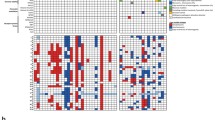

Analyzing whole-genome DNA methylation for multiple glial/glioneuronal tumor types, we confirmed our classifier results in which HGAP forms a distinct tumor type by unsupervised Uniform Manifold Approximation and Projection (UMAP) (Fig. 2A) and unsupervised hierarchical clustering (Supplemental Fig. 1). To identify potential distinct HGAP epigenetic subtypes in an unbiased fashion, we started with unsupervised hierarchical clustering analysis. This clustering led to the identification of three distinct HGAP epigenetic subtypes (Fig. 2b, Supplemental Fig. 2). Cluster subtyping was further supported by unsupervised dimensionality reduction using UMAP analysis (Fig. 2c). The smallest of the three groups (n = 18, 12.5%) was observed to contain a relatively high proportion of patients with a clinical diagnosis of Neurofibromatosis Type 1 (NF1) (p = 0.0008), and therefore this subtype was designated as group NF1 (gNF1) (Figs. 2, 3a). The other two subtypes were designated simply as Group 1 (g1; n = 72, 50.0%) and Group 2 (g2; n = 54, 37.5%). Although the gNF1 was enriched for patients with germline alterations, there was no difference in the frequency of NF1 alterations detected in the tumors across subtypes (Fig. 3b). However, given the fact that hypermethylation of the NF1 promoter region may be an alternate mechanism for NF1 inactivation [10], we evaluated for potential NF1 methylation differences across the three HGAP subtypes. Indeed, 5 of 30 (16.7%) of the CpG probes related to NF1 were differentially methylated in gNF1 when compared to the other subtypes (Fig. 3c).

HGAP resolves into three epigenetically determined subtypes. a Uniform Manifold Approximation and Projection (UMAP) dimensionality reduction confirms that HGAP forms a distinct methylation cluster when compared to other CNS glial/glioneuronal tumors. b Unsupervised hierarchical clustering heatmap of whole-genome CpG methylation for HGAP uncovers the presence of three distinct HGAP epigenetic subtypes. c UMAP dimensionality reduction of HGAP only confirms the presence of three HGAP subtypes. IT Infratentorial, ST supratentorial, PF posterior fossa, SC spinal cord)

NF1 germline status, somatic alterations, and NF1 methylation define a relevant HGAP subtype. a HGAP subtype gNF1 is enriched for patients having Neurofibromatosis Type 1 (NF1) (gNF1 = 33.3%, g1 = 6.9%, g2 = 3.6%) and b) ATRX alterations (gNF1 = 87.5%, g1 = 59.6%, g2 = 47.5%). b CDKN2A/B (gNF1 = 83.3%, g1 = 83.3%, g2 = 85.5%) and NF1 (gNF1 = 62.5%, g1 = 41.3%, g2 = 32.4%) alterations are common across HGAP subtypes. c There are 5 of 30 (16.7%) CpG probes in the NF1 regulatory region that are differentially methylated in the gNF1 subtype, 3 of which are in the gene enhancer region

Several clinical features beyond NF1 status tended to differ across HGAP subtypes. The initial tumors of gNF1, g1, and g2 subtypes had median ages of 43.5 years, 47.0 years, and 32.0 years, respectively (p > 0.05 for all pairwise comparisons, Mann–Whitney U tests, Fig. 4a, b). Only one of the twelve pediatric tumors was gNF1 subtype (Supplemental Table 2). Tumor localization varied among the three HGAP subtypes, with gNF1 having 100% of the tumors located in the posterior fossa (Fig. 4c, d). By contrast, subtypes g1 (35.4% supratentorial, 55.4% posterior fossa, 9.2% spinal cord) and g2 (29.2% supratentorial, 56.2% posterior fossa, 14.6% spinal cord) were found throughout the neuraxis (Fig. 4d). While HGAP subtype was associated with tumor location (chi-square, **p = 0.001) the significance was less than that of subtype association with NF1 syndrome. Furthermore, no association was observed between tumor location and NF1 syndrome (p = 0.359). Tumor location itself was not associated with difference in survival (Supplemental Fig. 3). Progression-free survival trended towards worse outcome for the gNF1 subtype when compared to the other two subtypes (Fig. 4e, f). The gNF1, g1, and g2 subtypes had median progression-free survival times of 252 days, 565 days, and 618 days, respectively. Overall survival appeared similar among all subtypes, although the number of patients with overall survival data was low (Fig. 4g, h). Three of the patients had recurrent tumors, all of which maintained their subtype assignment when compared to their original tumor. The first of these three patients had known Neurofibromatosis Type 1, with their original and two recurrent HGAPs all belonging to the gNF1 HGAP subtype. The other two patients did not have a clinical diagnosis of Neurofibromatosis Type 1. The second patient had paired initial and recurrent HGAP tumor in the g1 subtype while the third patient had paired initial and recurrent HGAP tumor in the g2 subtype.

In addition to NF1 alterations already discussed, we evaluated subtype-specific genetic changes in the other commonly altered genes ATRX and CDKN2A/B, as well as the novel TP53 mutants and NTRK2 gene fusion. ATRX alterations (as determined by immunohistochemistry and/or sequencing) were overrepresented (p = 0.023) in the gNF1 subtype (87.5%) when compared to the g1 and g2 groups (59.6% and 47.5%, respectively) (Fig. 3b). No difference in CDKN2A/B deletion status was observed across HGAP subtypes (p = 0.949), with all subtypes having a high frequency of alterations (gNF1 = 84.2%, g1 = 83.3%, g2 = 85.5%) (Fig. 3b). Of the five novel TP53 mutant cases we found, four were present in the g1 subtype, one was in g2, and none were found in the gNF1 subtype. The sole NTRK2 gene fusion positive HGAP was present in the g2 subtype.